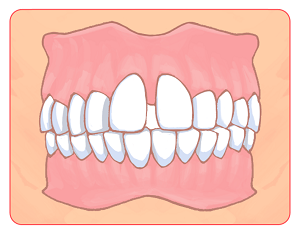

「いびき」と「口輪筋」の関係

「いびき」と「口輪筋」の関係